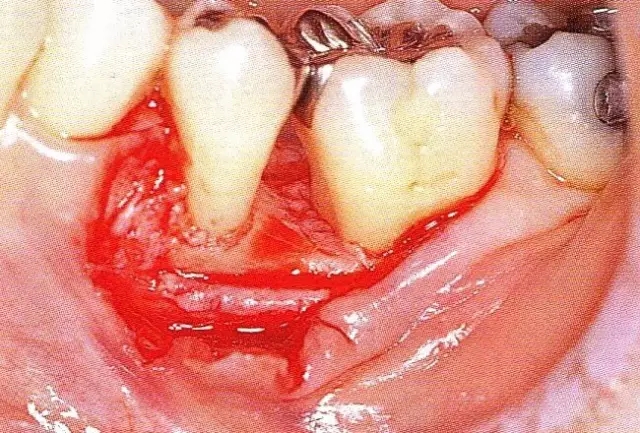

▲圖7-3  將posterior interproximal類型的非吸收性覆膜修整后進行垂直懸吊縫合做固定。垂直懸吊縫合后,確定覆膜是否會動搖,再將齦瓣與之緊密縫合。